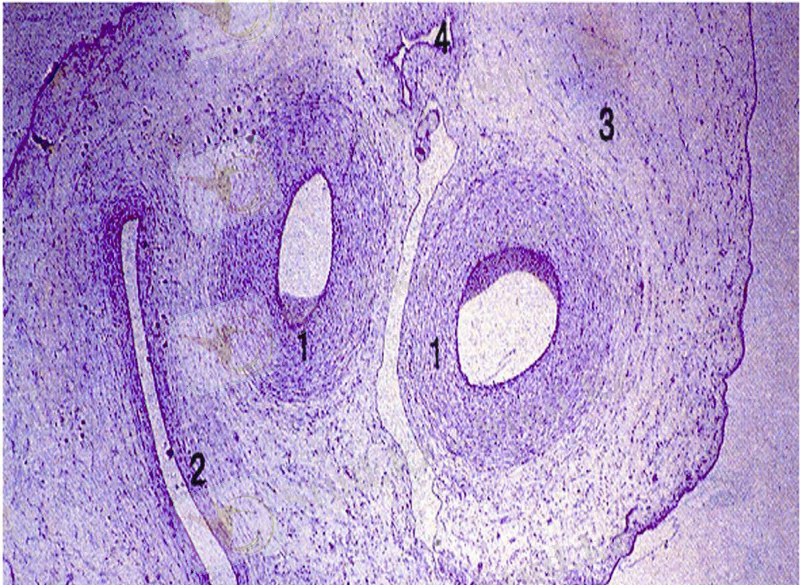

1. Прогенез

2. Жыныс жасушаларының құрылысы

ПРОГЕНЕЗ